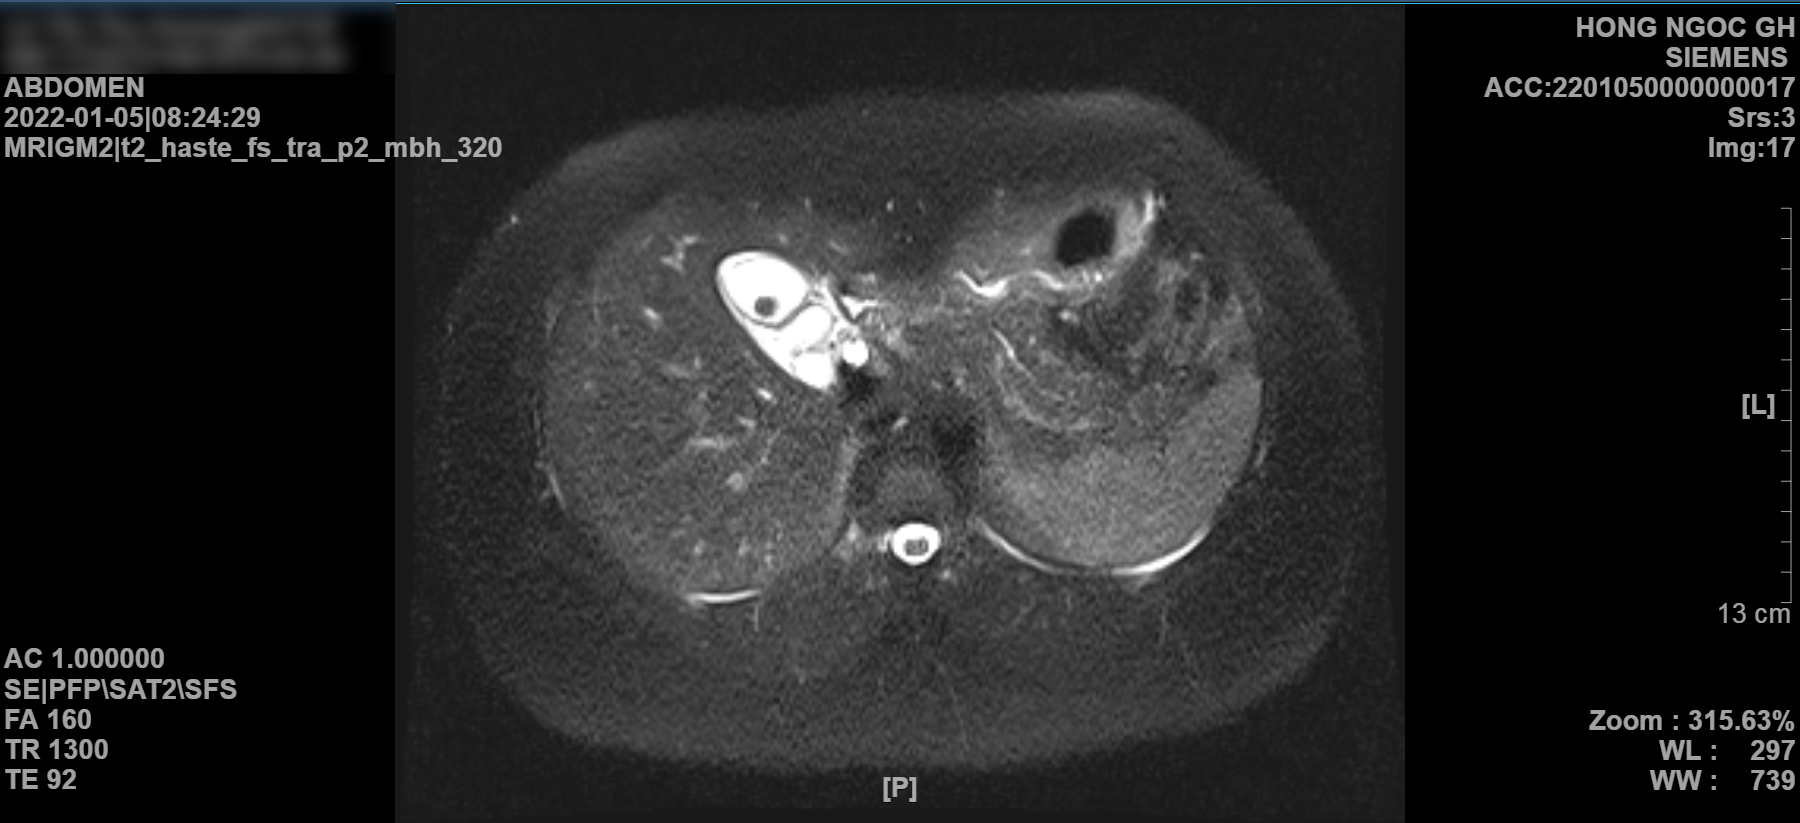

width= Hình ảnh MRI túi mật có sỏi của chị L.T.T.Hòa trước khi phẫu thuật

Chị Hòa nhớ lại: “Gần nhà chị có bệnh viện thế nhưng rút kinh nghiệm từ lần bệnh trước của chồng, chị quyết tâm đến Bệnh viện Hồng Ngọc dù có hơi xa một chút. Từ 06 năm nay, nhà chị đã tin tưởng lựa chọn Hồng Ngọc. Phải công nhận là các bác sĩ ở đây rất có chuyên môn. Ngay từ thăm khám ban đầu, bác sĩ khám và ấn vị trí bụng là đã nghi ngờ chị bị viêm túi mật do sỏi rồi. Lúc đó chị vẫn phân trần với bác sĩ là mình bị viêm dạ dày vì có tiền sử mà. Thế nhưng, kết quả chụp MRI thì đúng là mình bị sỏi mật thật. Cũng rất may là các bác sĩ chẩn đoán chính xác, xử lý nhanh. Ngay hôm đó là chị đã được phẫu thuật xong, đến chiều là khỏe luôn và có thể ngồi dậy rồi.

Chẩn đoán xác định viêm túi mật cấp tính do sỏi được thực hiện thông qua các phương pháp chẩn đoán bằng hình ảnh như siêu âm/chụp MRI. Thậm chí, nhiều bác sĩ cũng có thể phát hiện viêm túi mật cấp tính do sỏi nhờ chẩn đoán tiền lâm sàng dựa theo các triệu chứng của bệnh. Tuy nhiên, tất cả phải được thực hiện tại các cơ sở y tế uy tín và bác sĩ tiêu hóa có kinh nghiệm bởi đã từng có nhiều trường hợp bệnh nhân lâm vào tình trạng nguy hiểm đến tính mạng do chẩn đoán và điều trị sai.